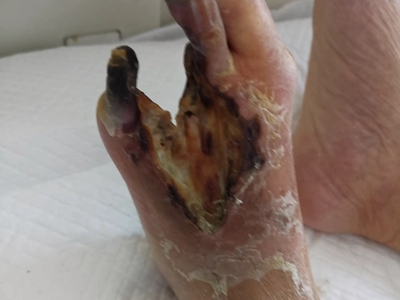

坏疽是指局部组织大块坏死并继发腐败菌感染,而湿性坏疽是坏疽的一种类型,多发生于与外界相通的内脏,也可发生于肢体如足部,临床常见糖尿病足坏疽。局部皮肤可出现充血、肿胀、溃疡,肿胀部位呈蓝绿色。本病主要通过清创、引流等方法进行处理。

湿性坏疽多发生于与外界相通的内脏,如肺、肠、子宫、阑尾及胆囊等,也可发生于动脉阻塞及静脉回流受阻的肢体,临床常见糖尿病足坏疽。局部皮肤充血、肿胀、溃疡甚至严重坏疽,坏死区水分较多,腐败菌易于繁殖,故肿胀呈蓝绿色,且与周围正常组织界限不清。

湿性坏疽多是继发于血液循环障碍引起的缺血坏死,常见于糖尿病足,诱因为皮肤外伤、烫伤、鞋袜不合适、感染等。